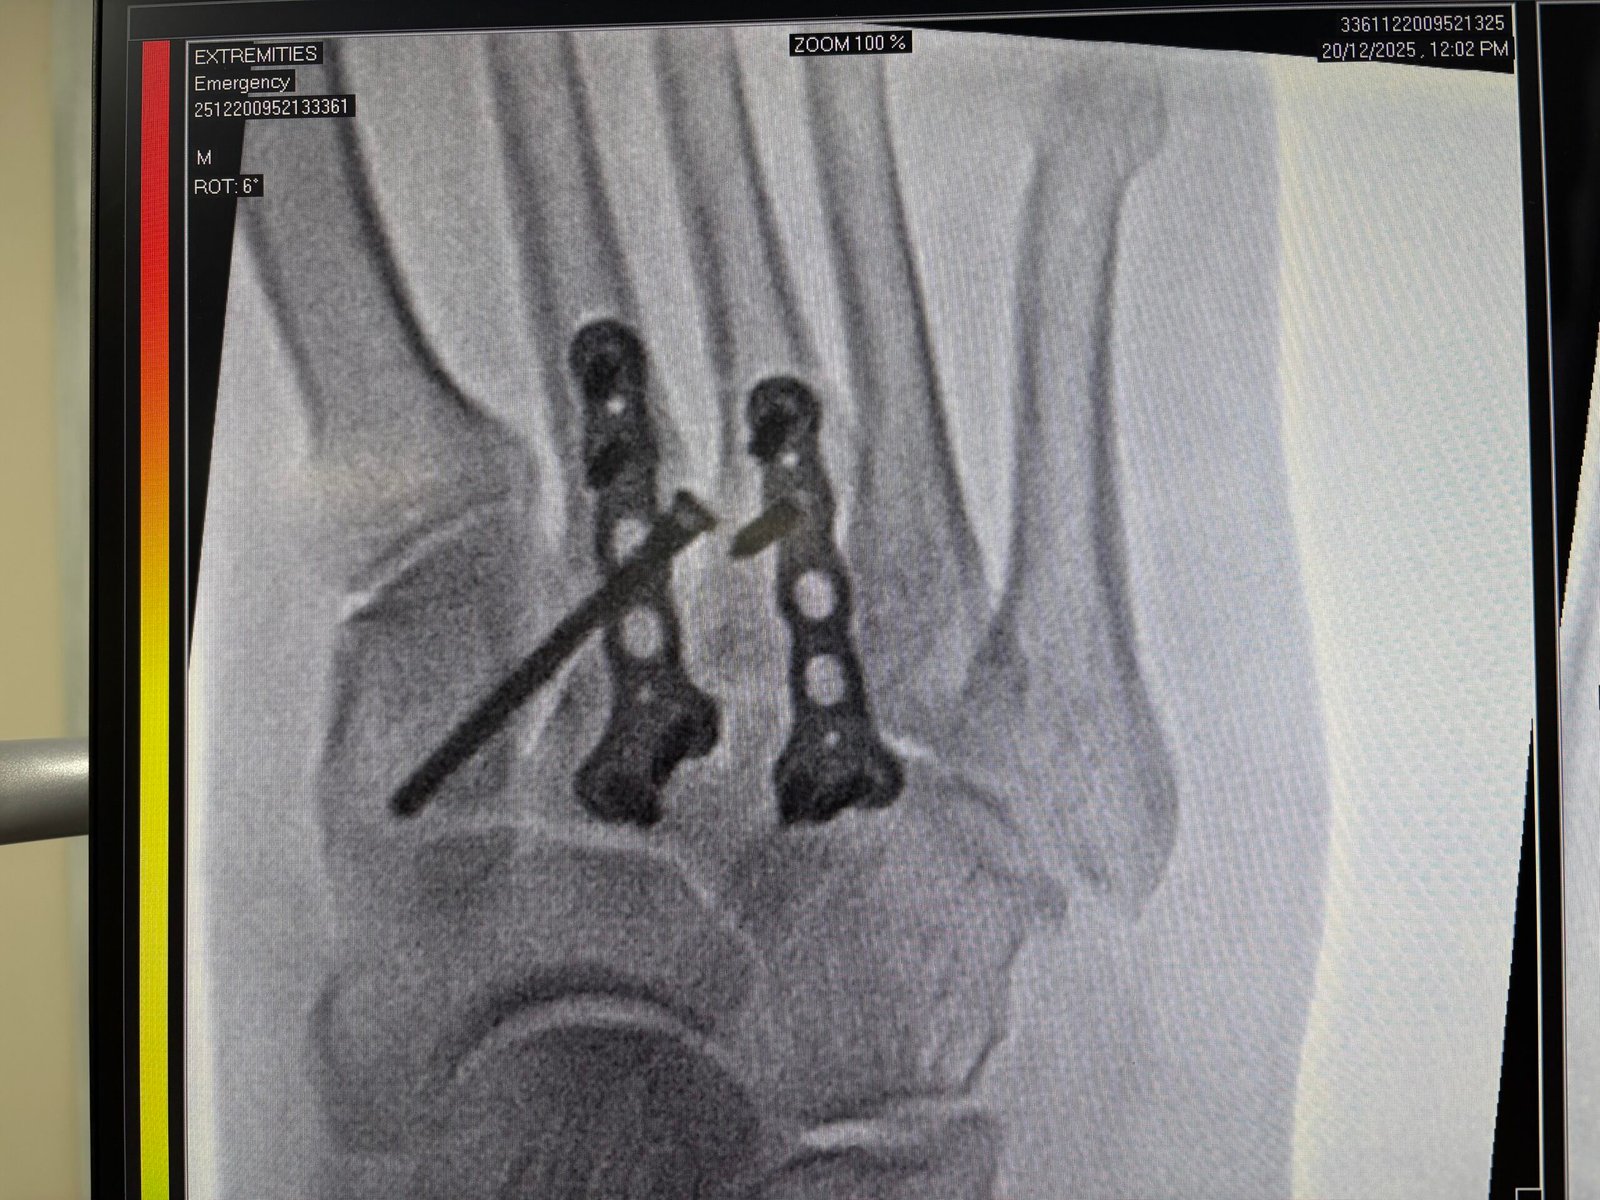

Orthopedic Trauma and Fracture Fixation

Expert management of complex fractures and accidental injuries with a focus on rapid recovery. We provide 24/7 emergency stabilization followed by advanced fixation or non-surgical bracing as required.

Hand, Foot & Ankle Specialist

Precise care for intricate bone and nerve issues of the extremities. Whether treating a sports sprain or a complex deformity, we focus on restoring the fine functionality needed for your daily life.